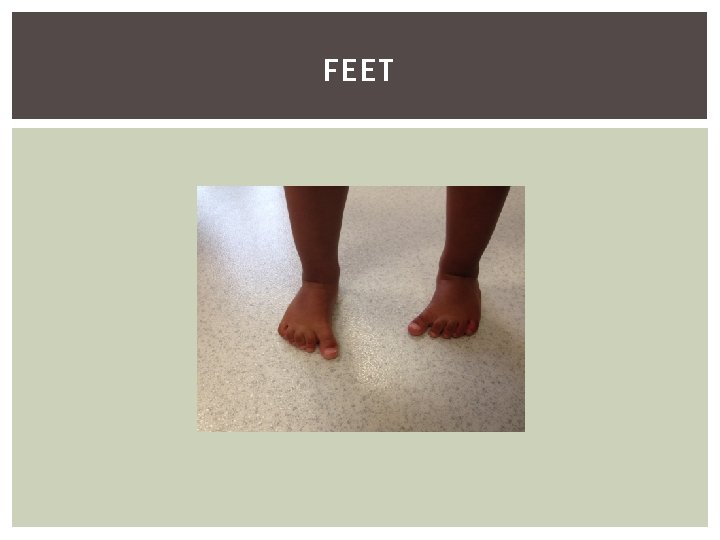

FEET

COMMON CONDITIONS Metatarsus Adductus Calcaneo-Valgus CTEV Curly toes Flat Foot Tarsal Coalition Pes Cavus Severs

FOOT - ASSESSMENT